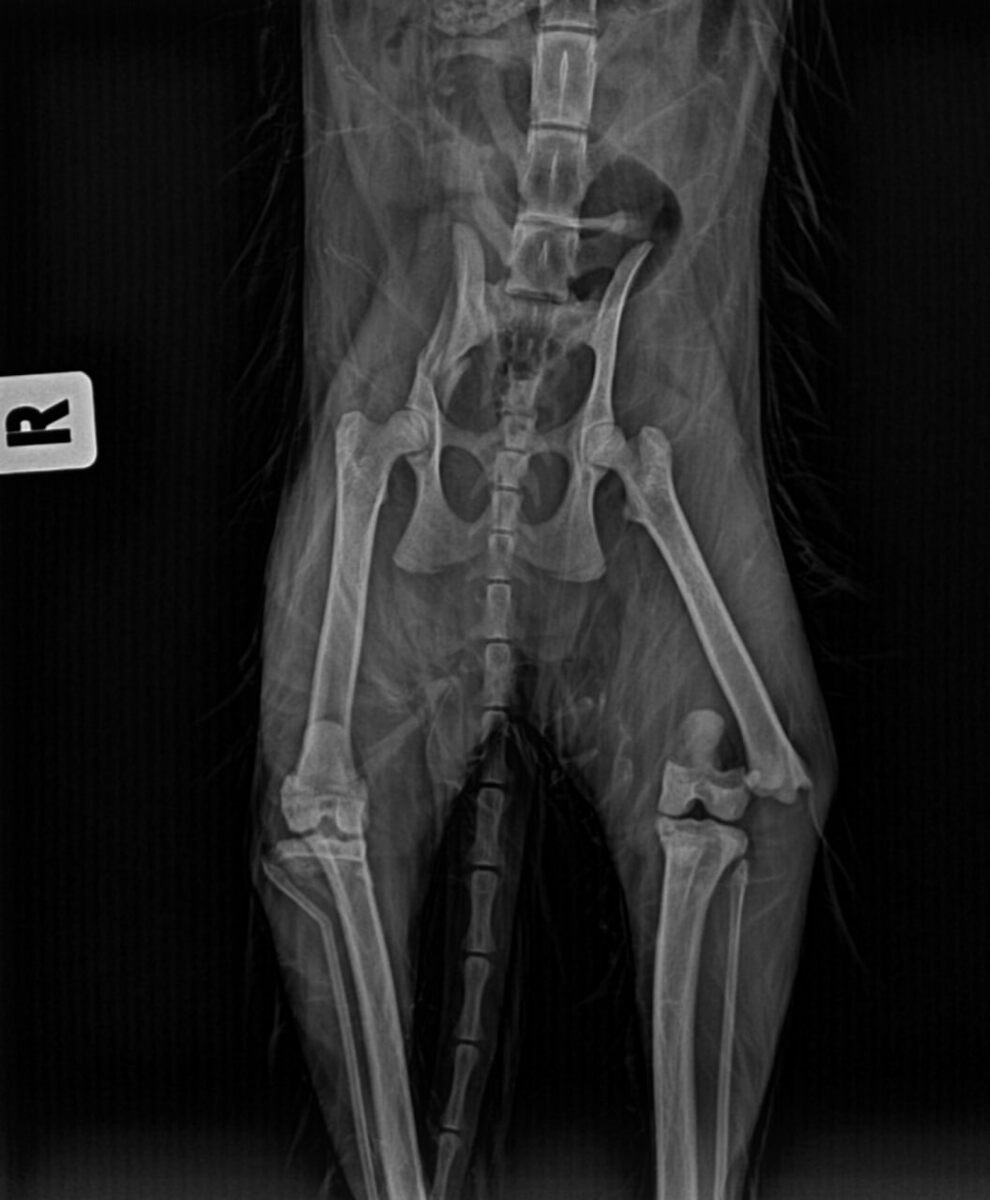

Ватрушка...Малышка с тяжелыми повреждениями... Я не знаю, что с ней случилось. Возможно, автотравма. Или падение с высоты. Но обе задние лапки сломаны, одна раздроблена. Сломан таз. Проблемы с маленьким сердечком. Пневмоторакс. И все беды на одного маленького котёночка...

Сегодня девочку прооперировали. В одну лапку поставили штифт, другую зафиксировали. Таз оставили на самостоятельное заживление, ибо там нет смещения. Малышка очень слабенькая. Даже уже не знаю, кому молиться, чтобы она выкарабкалась...